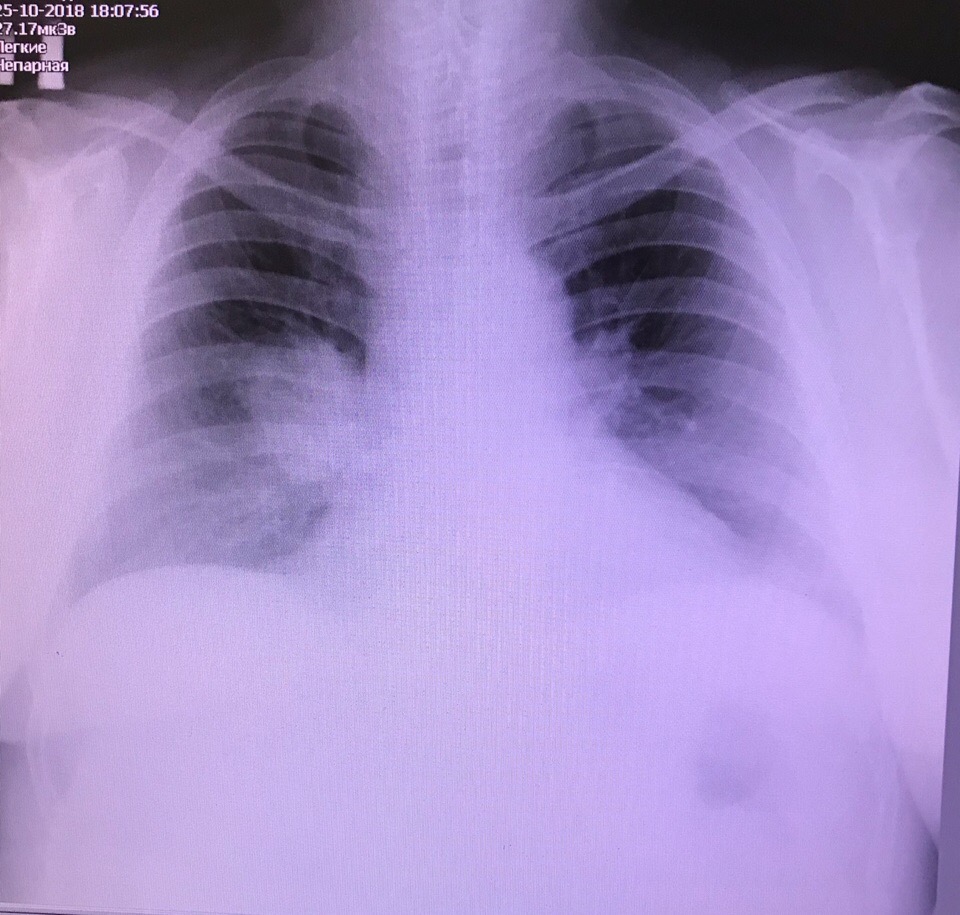

Центральный рак справа. Обсуждалось здесь https://vk.com/club84409679?w=wall-84409679_9290%2Fall

pixCipeklss.jpg

pixCipeklss.jpg [ 212.28 KiB | Просмотров: 10593 ]